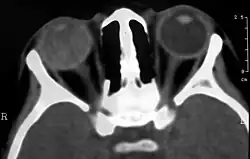

Choroba Coatsa (łac. teleangiectasis retinae, morbus Coats, ang. Coats' disease, exudative retinitis, retinal telangiectasis) – wrodzone, niedziedziczne, postępujące uszkodzenie naczyń krwionośnych siatkówki. Choroba może przypominać przebiegiem siatkówczaka[2]. Schorzenie opisał jako pierwszy szkocki okulista George Coats w 1908 roku[3].

W ciężkich postaciach choroba objawia się masywnymi wysiękami z wtórnym odwarstwieniem siatkówki. Może wystąpić biały refleks źreniczny (leukokoria), zez i niedowidzenie. W lżejszych postaciach objawem jest obniżenie ostrości wzroku.